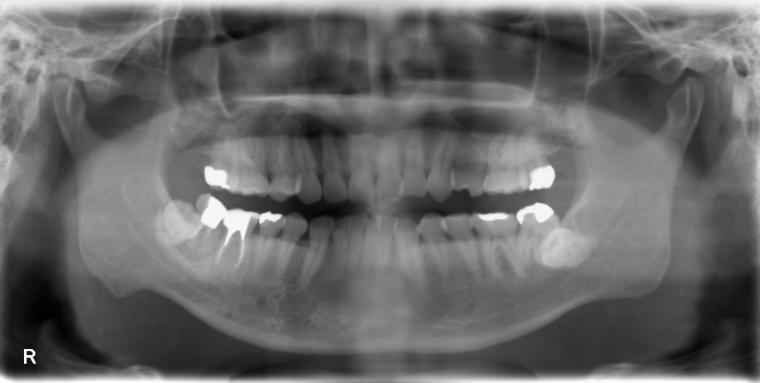

BEFORE

38歳男性/下1本欠損/インプラント埋込手術

右下奥歯が虫歯になってしまった為治療をすることになった患者さんです。

虫歯が進行していて、歯を保存出来なかったため歯を抜いて人工の骨を足してからインプラントを

1本埋込した患者さんです。